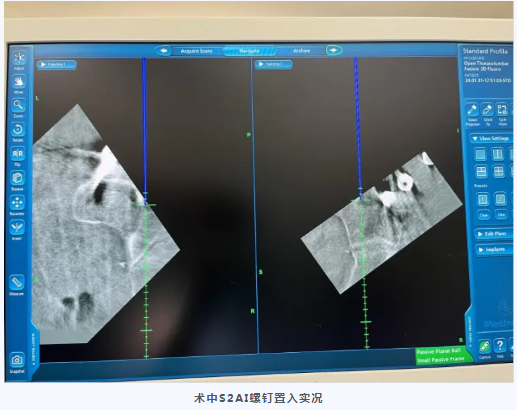

S2AI为经骶2骶髂螺钉,置入后与近端腰椎椎弓根钉保持在同一纵线上,连接方便,而且不存在钉尾突兀刺激皮肤的问题,近年来已成为备受推崇的腰骶固定方式,但一直以来S2AI螺钉的置入都极具挑战性。此例患者软组织丰厚,腰骶段暴露困难,更加大了置钉难度。C臂导航对S2AI置入的准确度和安全性具有非常明显的优势,大大降低了以往仅仅根据术者经验完成手术的风险,实现了数字化、精准化的质的飞跃。在清晰的图像指引下,经过3小时的精细操作,成功为这位病情复杂的患者施行了手术。整个手术过程出血量少,S2AI螺钉置入精准,病灶清除彻底。术后患者顺利康复。